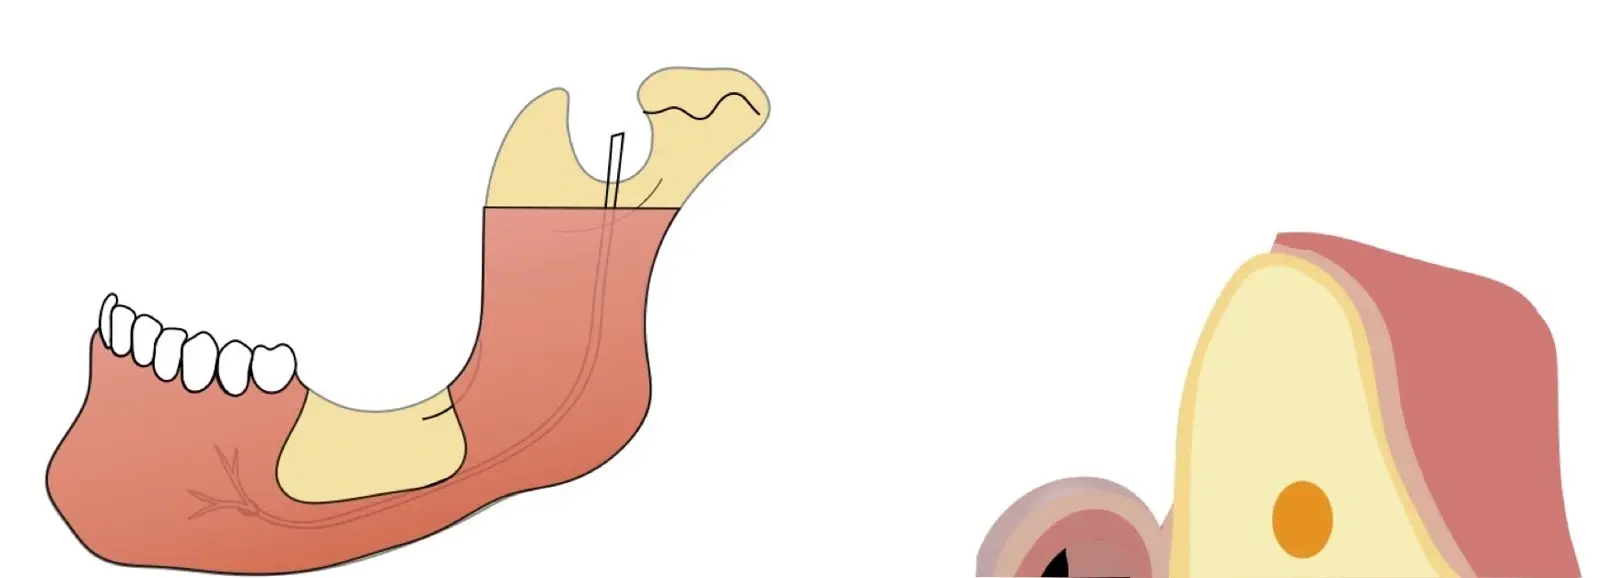

Figura 1. Evaluación clínica: zona donadora (a) y zona receptora (b).

Aplicaciones clínicas: Injerto autólogo en bloque para reconstrucción de reborde

Si la zona donadora es la sínfisis mentoniana, se deben tomar en cuenta los límites de seguridad para la extracción del injerto, que son 5 mm alejado de los ápices, y 5 mm alejado del agujero mentoniano (Figuras 2 y 3).